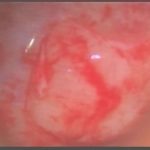

術中写真

摘出 中